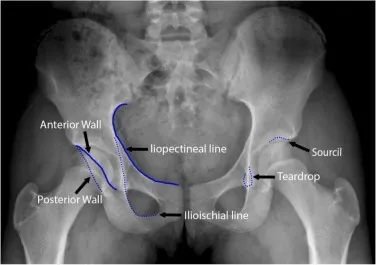

Key Radiographic Lines - Connect the Dots

Shenton's Line: A smooth, continuous arc from the medial aspect of the femoral neck to the inferior border of the superior pubic ramus. Disruption is a key sign of a femoral neck fracture or developmental dysplasia of the hip (DDH).

Iliopectineal Line: Follows the pelvic brim, representing the anterior column of the acetabulum. A break suggests an anterior column fracture.

Ilioischial Line (Kohler's Line): Represents the posterior column of the acetabulum. Disruption points to a posterior column fracture.

Acetabular Landmarks - Hip Socket Scoop

- Key lines on an AP pelvis X-ray that assess the integrity of the acetabulum.

- Iliopectineal Line: Represents the anterior column.

- Ilioischial Line: Represents the posterior column.

- Radiographic Teardrop: Formed by the medial wall of the acetabulum.

- Shenton's Line: A continuous curve along the inferior border of the femoral neck and the superior pubic ramus. Disruption suggests fracture or dislocation.

- Acetabular Roof (Sourcil): The weight-bearing dome.